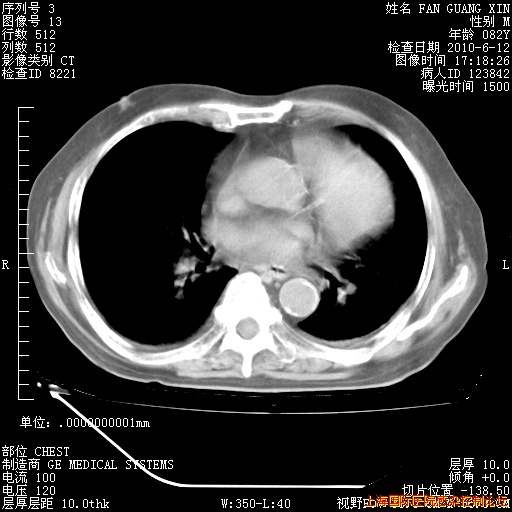

6月12日纵膈窗

补发6月12日肺部CT肺窗

6月12日肺窗